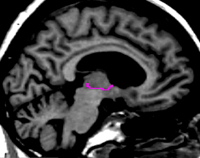

The hypothalamic fissure serves as the inferior border of the thalamus and a dividing line between the thalamus and the ventral diencephalon (VDC). This border is marked by drawing sulci in the medial sagittal views of the thalamus and VDC. The hypothalamic fissure is seen most easily toward the midline in the sagittal view, therefore begin drawing the sulci lines on or close to the most medial sagittal slice. The fissure should be drawn as a line which cups the bottom of the thalamus beginning caudally and moving rostrally as far as possible. It is often advantageous to draw many sulci on consecutive sagittal slices, moving from medial to lateral, in order to see the full extent and curve of the fissure more accurately in the coronal view.